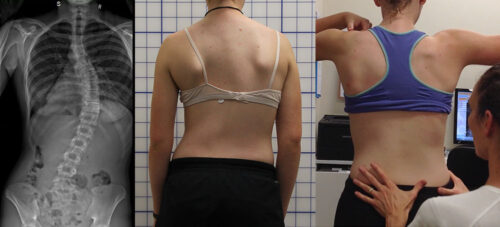

عندما يُشخَّص طفلك أو مراهقك بإصابة في العمود الفقري تُعرف بالجنف أو اعوجاج العمود الفقري، يتساءل الكثير من الأهل فورًا: “هل يحتاج طفلي إلى جراحة؟” هذا القلق طبيعي جدًا، خاصة مع كثرة المعلومات المتضاربة على الإنترنت.

الحقيقة المُطمئنة: في أغلب الحالات يمكن علاج اعوجاج العمود الفقري دون اللجوء للجراحة، خصوصًا عند الاكتشاف المبكر واتباع خطة علاجية صحيحة ومتابعة مستمرة.

العلاج غير الجراحي يتطلب التزامًا من الأهل والمريض ومراقبة دقيقة للانحناء باستخدام الأشعة وتحليل زاوية “كوب” (Cobb Angle). هذه المتابعة تضمن تعديل خطة العلاج بما يتناسب مع تطور الحالة.

اكتشفوا الانحناء مبكرًا بمراجعة الطبيب والفحص الدوري.

تابعوا قياسات زاوية “كوب” لضمان فعالية العلاج.

الاعوجاج حالة مستمرة ولهذا السب قد تحتاج تدخلًا في مراحل مختلفة من العمر. وبفضل وجود تقنيات التصنيف المعتمدة ، يمكن للأطباء تصميم خطة علاجية مخصصة تضمن تدخلاً جراحيًا عند الضرورة أو العلاج غير الجراحي قبل ذلك، لتفادي الاضطراب في الوظائف التنفسية أو أي أعراض متأخرة. فريقنا المحترف يضم نخبة من الأطباء والمتخصصين الذين يجمعون بين الخبرة والاحترافية لتقديم خطة علاجية شاملة ومخصصة لحالتك، تضمن السيطرة على الانحناء ومنع زيادته.